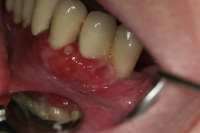

Förekomst av gingivala hyperplasier med djupa tandköttsfickor och svåra hygienförhållanden som följd.

Läkemedelsinducerad gingival hyperplasi:

En volymökning av mjukvävnaden kring tänderna som är associerad med intag av läkemedel tillhörande grupperna antiepileptika, immunosuppressiva läkemedel och kalciumblockerare.

Inflammation är den utlösande faktorn som driver tillväxten av mjukvävnaden därför är plackkontroll av största vikt.